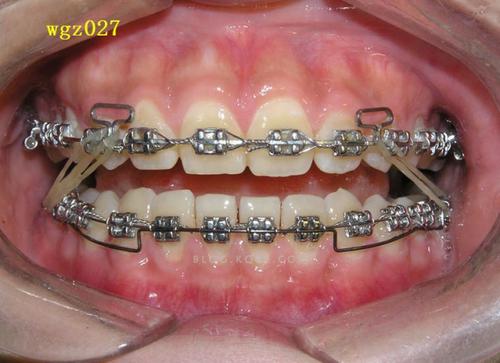

压低辅弓的核心在于通过弓丝的形变产生持续、轻柔的压低力,同时避免牙齿发生不必要的倾斜或旋转,其结构通常包括主弓丝和辅弓两部分:主弓丝(如不锈钢丝或β钛丝)提供基础支抗,辅弓(多为镍钛丝或澳丝)通过特定的弯曲形态(如“Ω”形曲、垂直曲)与托槽或附件连接,当辅弓被激活后,产生的力量通过托槽传递至牙冠,作用于牙槽骨,引导牙槽骨改建,实现牙齿压低。

力学控制是关键:辅弓的设计需确保力量中心位于牙根长轴附近,避免产生过大的力矩导致牙齿倾斜,针对前牙压低,辅弓常在侧切牙远中弯制停止曲,配合牵引钩与颌骨或后牙支抗装置连接,形成“压低-支抗”平衡系统;而后牙压低则需辅弓与磨牙带环或种植支抗钉协同,通过后牙垂直向移动为前牙压低提供空间。

- 形态设计:前牙压低辅弓常呈“”形,在侧切牙远中弯制垂直曲,配合牵引钩与颌骨或腭杆连接;后牙压低辅弓则需在磨牙区弯制后倾曲,与磨牙带环或种植钉形成锚固。

粘接附件与施力

- 附件粘接:目标牙需粘接标准方丝弓托槽或专用压低托槽,确保托槽高度和位置准确(如前牙托槽粘接高度需参考牙龈缘,避免压迫牙龈)。

- 辅弓安装与激活:将辅弓插入托槽,通过弯制曲部或调整牵引钩位置激活力量,初始力量控制在50-100g(避免过大力量导致牙根吸收或疼痛),每4-6周复诊调整一次。